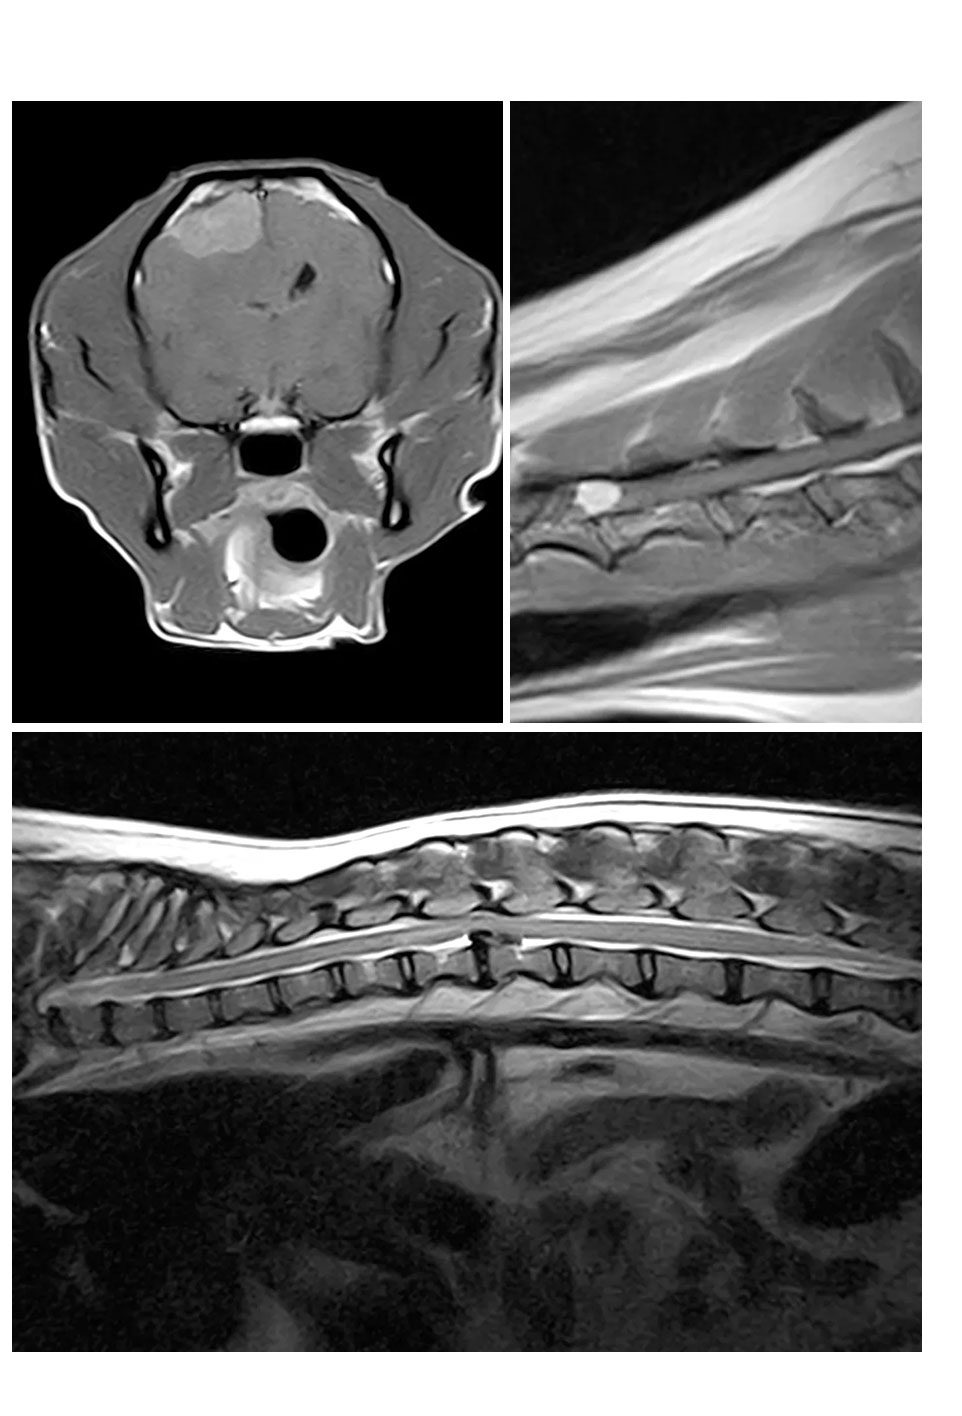

• ECOGRAFIA,  TC,  RM

• CHIRURGIA SPECIALISTICA